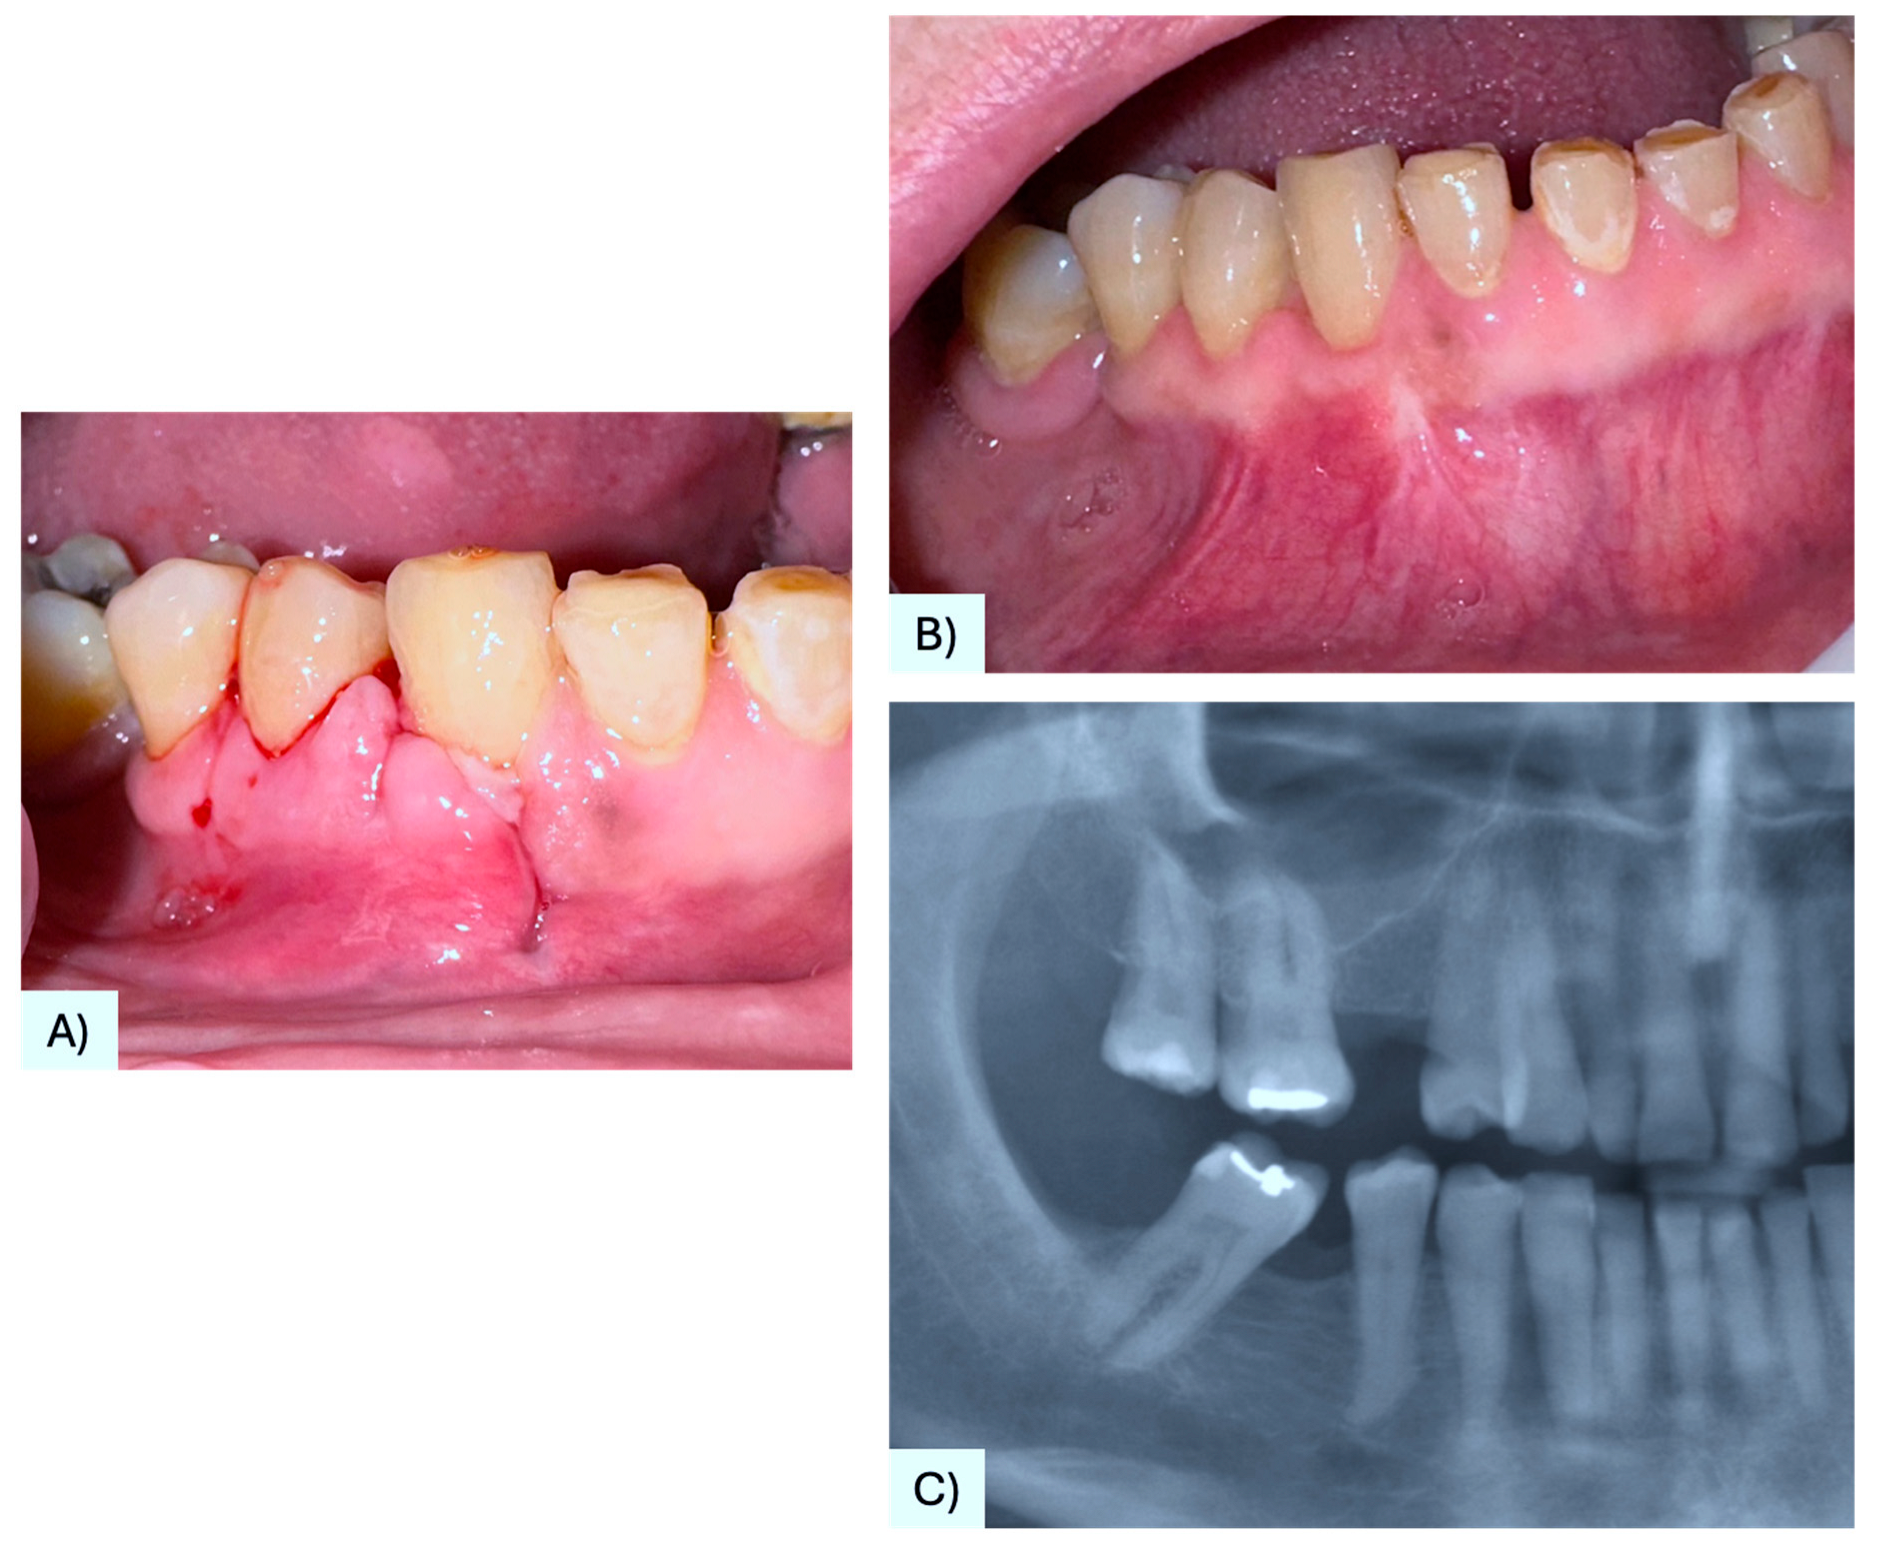

| 33 | Lado Lako Loro et al. [25] | 33 F | Maxilla, gingiva between #1.3, #1.5 | Asymptomatic nodule | 3 mm | None | Alveolar bone resorption | Excision | No evidence after 10 months | 2023 |